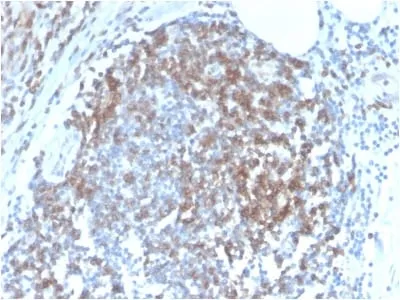

Flow (verified) | IF (verified) | IHC, FFPE (verified)Validated Applications:

ImmunologyPositive Control:

Higher concentration may be required for direct detection using primary antibody conjugates than for indirect detection with secondary antibody|Immunohistology (formalin): 0.5-1 ug/mL for 30 minutes at RT|Staining of formalin-fixed tissues requires boiling tissue sections in 10 mM citrate buffer, pH 6.0, for 10-20 minutes followed by cooling at RT for 20 minutes|Optimal dilution for a specific application should be determined by userShipping Conditions: